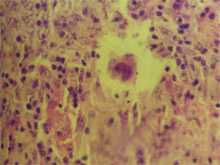

误诊为坏死性肉芽肿的结外NK/T细胞淋巴瘤1例

病例

2025-02-05